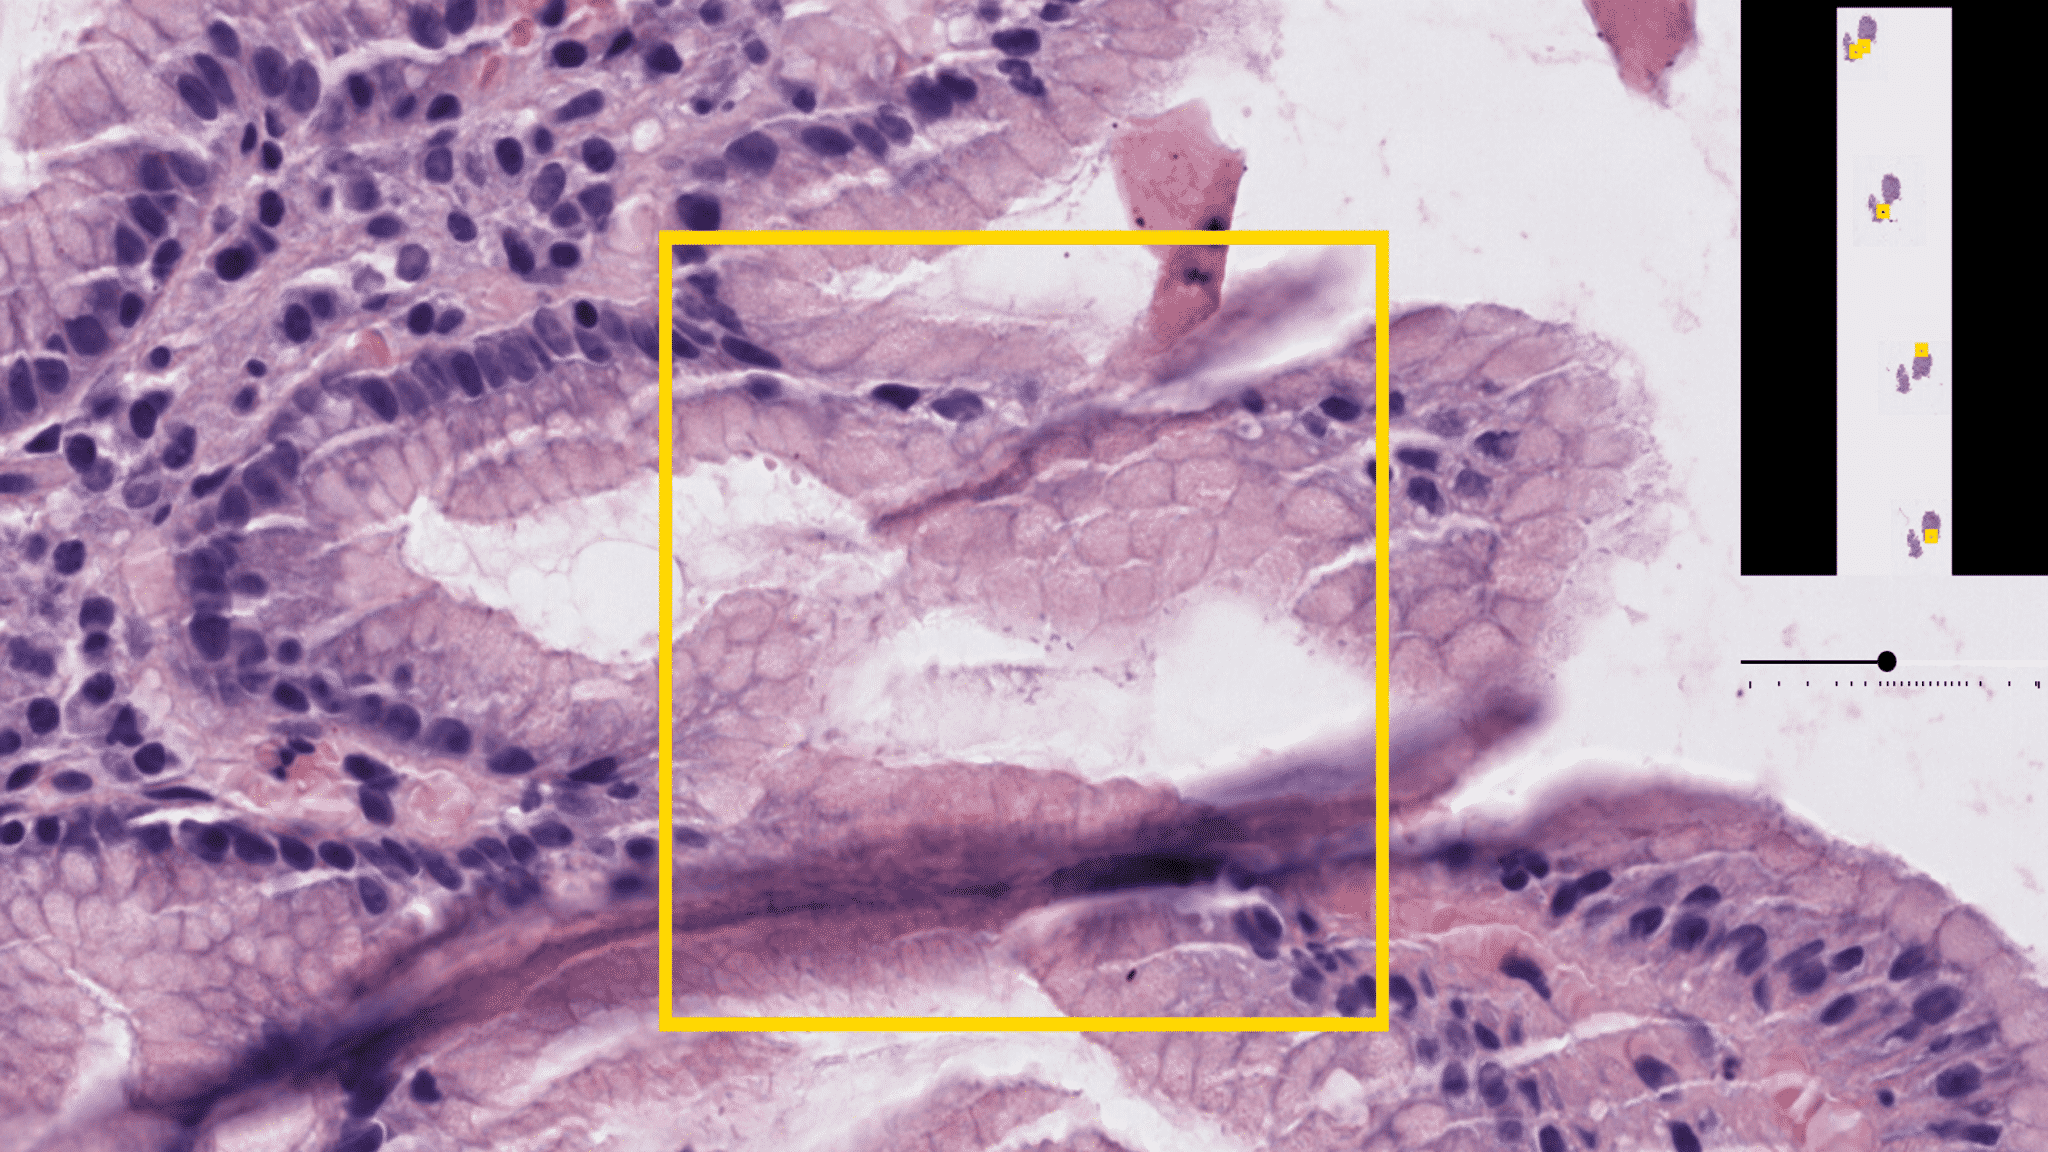

The Helicobacter Pylori (H.Pylori), a germ that’s known to cause inflammation, gastritis, and ulcers, is lurking in the stomachs of a staggering 50% of the global population. When people go through gastric biopsies, part of the protocol is to look for the H.Pylori germ because it can lead to cancerous outcomes and diseases in the upper intestinal tract if left untreated - otherwise, it’s eradicated with antibiotic treatments. Unfortunately for Pathologists, the identification process is manual: a Pathologist scans through magnified digital gastric slides with Haemotoxylin and Eosin (H&E) and Giemsa stains to identify the germ. DeePathology.ai is setting out alleviate the Pathologist’s workload albeit with the highest likelihood of widespread hospital adoption. Such a goal requires the unique expertise of AI research and hardware optimization.

“We are using deep learning algorithms to support the Pathologist” explained Jacob. “In the case of the H.Pylori detection, our algorithm scans the slides and marks each region with a score of presence of H.Pylori. Then the highest scoring regions can be reviewed by a Pathologist and can be quickly confirmed. For difficult and ambiguous cases, slides can be sent to further expensive tests like IHC staining or PCR. Using our algorithm execute this selection makes it very economical since the hospitals don’t have to send all the slides to these expensive tests.”